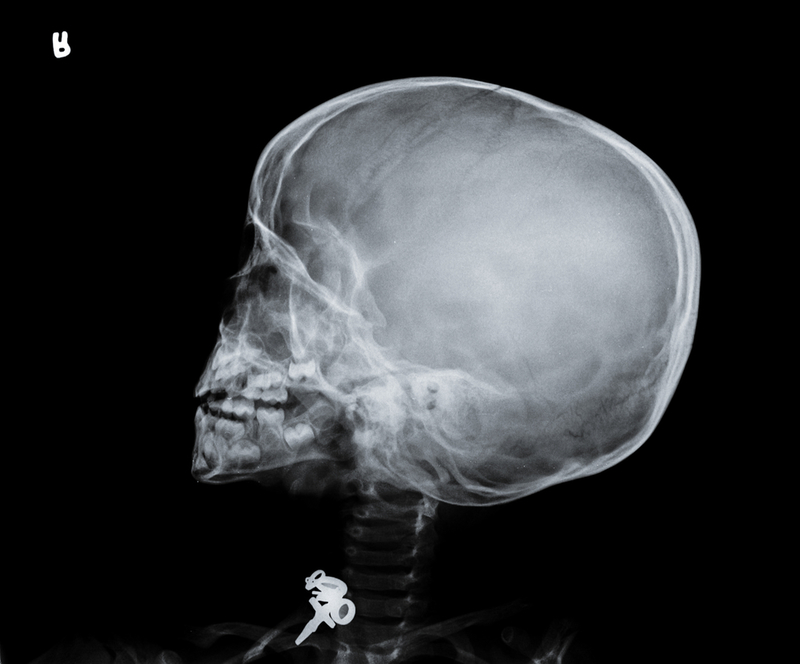

The 3.4-million pounds project, funded by the National Institute of Health Research, will be conducted over four years by researchers from institutions in the UK and India. It will study around 80,000 women recruited from three major hospitals in South India the Bangalore Medical College, the Madras Medical College and the Calicut Medical College. All babies with brain injury will have detailed neurophysiological investigations, including electroencephalogram (EEG), advanced magnetic resonance imaging (MRI) and neurodevelopmental follow up assessments.